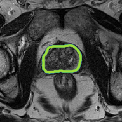

Despite their outstanding accuracy, semi-supervised segmentation methods based on deep neural networks can still yield predictions that are considered anatomically impossible by clinicians, for instance, containing holes or disconnected regions. To solve this problem, we present a Context-aware Virtual Adversarial Training (CaVAT) method for generating anatomically plausible segmentation. Unlike approaches focusing solely on accuracy, our method also considers complex topological constraints like connectivity which cannot be easily modeled in a differentiable loss function. We use adversarial training to generate examples violating the constraints, so the network can learn to avoid making such incorrect predictions on new examples, and employ the Reinforce algorithm to handle non-differentiable segmentation constraints. The proposed method offers a generic and efficient way to add any constraint on top of any segmentation network. Experiments on two clinically-relevant datasets show our method to produce segmentations that are both accurate and anatomically-plausible in terms of region connectivity.